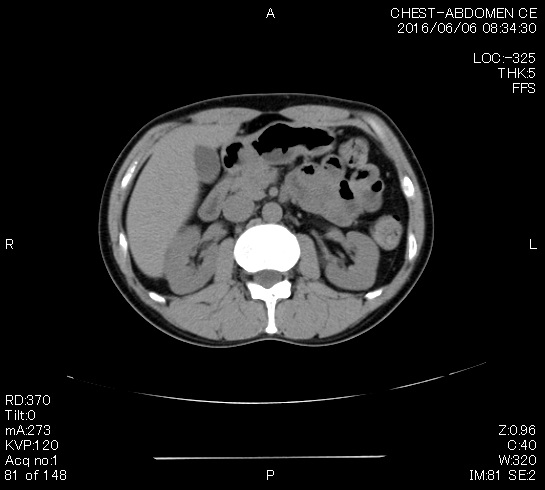

CTとマーカーは問題なし。 先生は「もう検査しなくても~」と言い始めたので、「昨年のマーカー上昇が気になるのですが、年一でマーカーは意味ないですか?」と伝えたら、「じゃあCTも撮ろうよ」ということで、結局次回は1年後となった。 結果はマーカー:陰性、CTも問題なし!

落ち着いたということで、次回は半年後の12月。

マーカーは超久しぶりの陰性(0.1未満)だった。

2020年8月に陽性になったので、実に1年7ヵ月ぶりの陰性。 次は6月にCTとマーカー。 腫瘍マーカーの結果は安定の0.1(笑)。